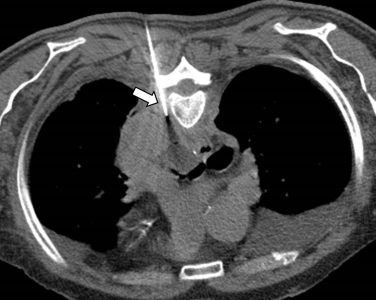

Ακτινολογία

Διαδερμικά κατευθυνόμενη βιοψία παρα-αορτικού λεμφαδένα σε λέμφωμα Hodgkin